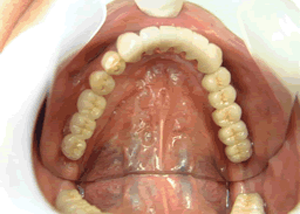

4.下14本最終の冠をかぶせたところ-上から(鏡)

-正面-下14本の最終の冠をかぶせたところ